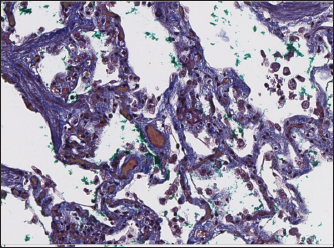

Immunohistochemical labeling with anti-CD31 antibody and anti-factor von Willebrand antibody showed wide dispersion between the groups. In the RHF group, we found a weak-to-absent reaction for the CD31 marker in most of the fibrotic fields, restricted to endothelial cells. Additionally, we discovered an intensive reaction to von Willebrand factor in most arterioles and in vessels with plexiform morphology. In sPCH animals, we observed significant expression of CD31 marker covering most of the fields and actively present in alveolar septae with numerous capillaries. However, the representation of von Willebrand factor was almost absent (Figs. 6 and 7).

Fig. 7. sPCH group. Immunohistochemistry. Left—active expression of CD31 marker in numerous endothelial cells in alveolar septae. Right—almost absent of factor von Willebrand expression in cells.